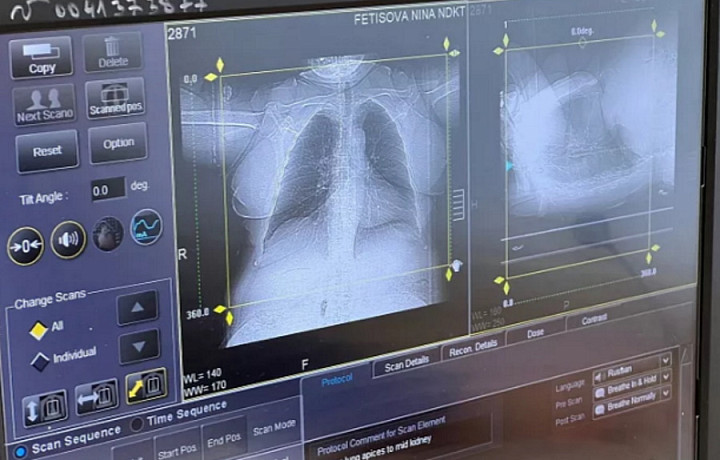

У семи жителей Тульской области врачи выявили подозрение на рак во время Дня открытых дверей в поликлинике областного онкодиспансера.

Как сообщает пресс-служба регионального минздрава, около 140 туляков обследовались и проконсультировались с онкологом.

В рамках диагностики у семи человек было обнаружено подозрение на рак. Пациентов отправили на дополнительные обследования.